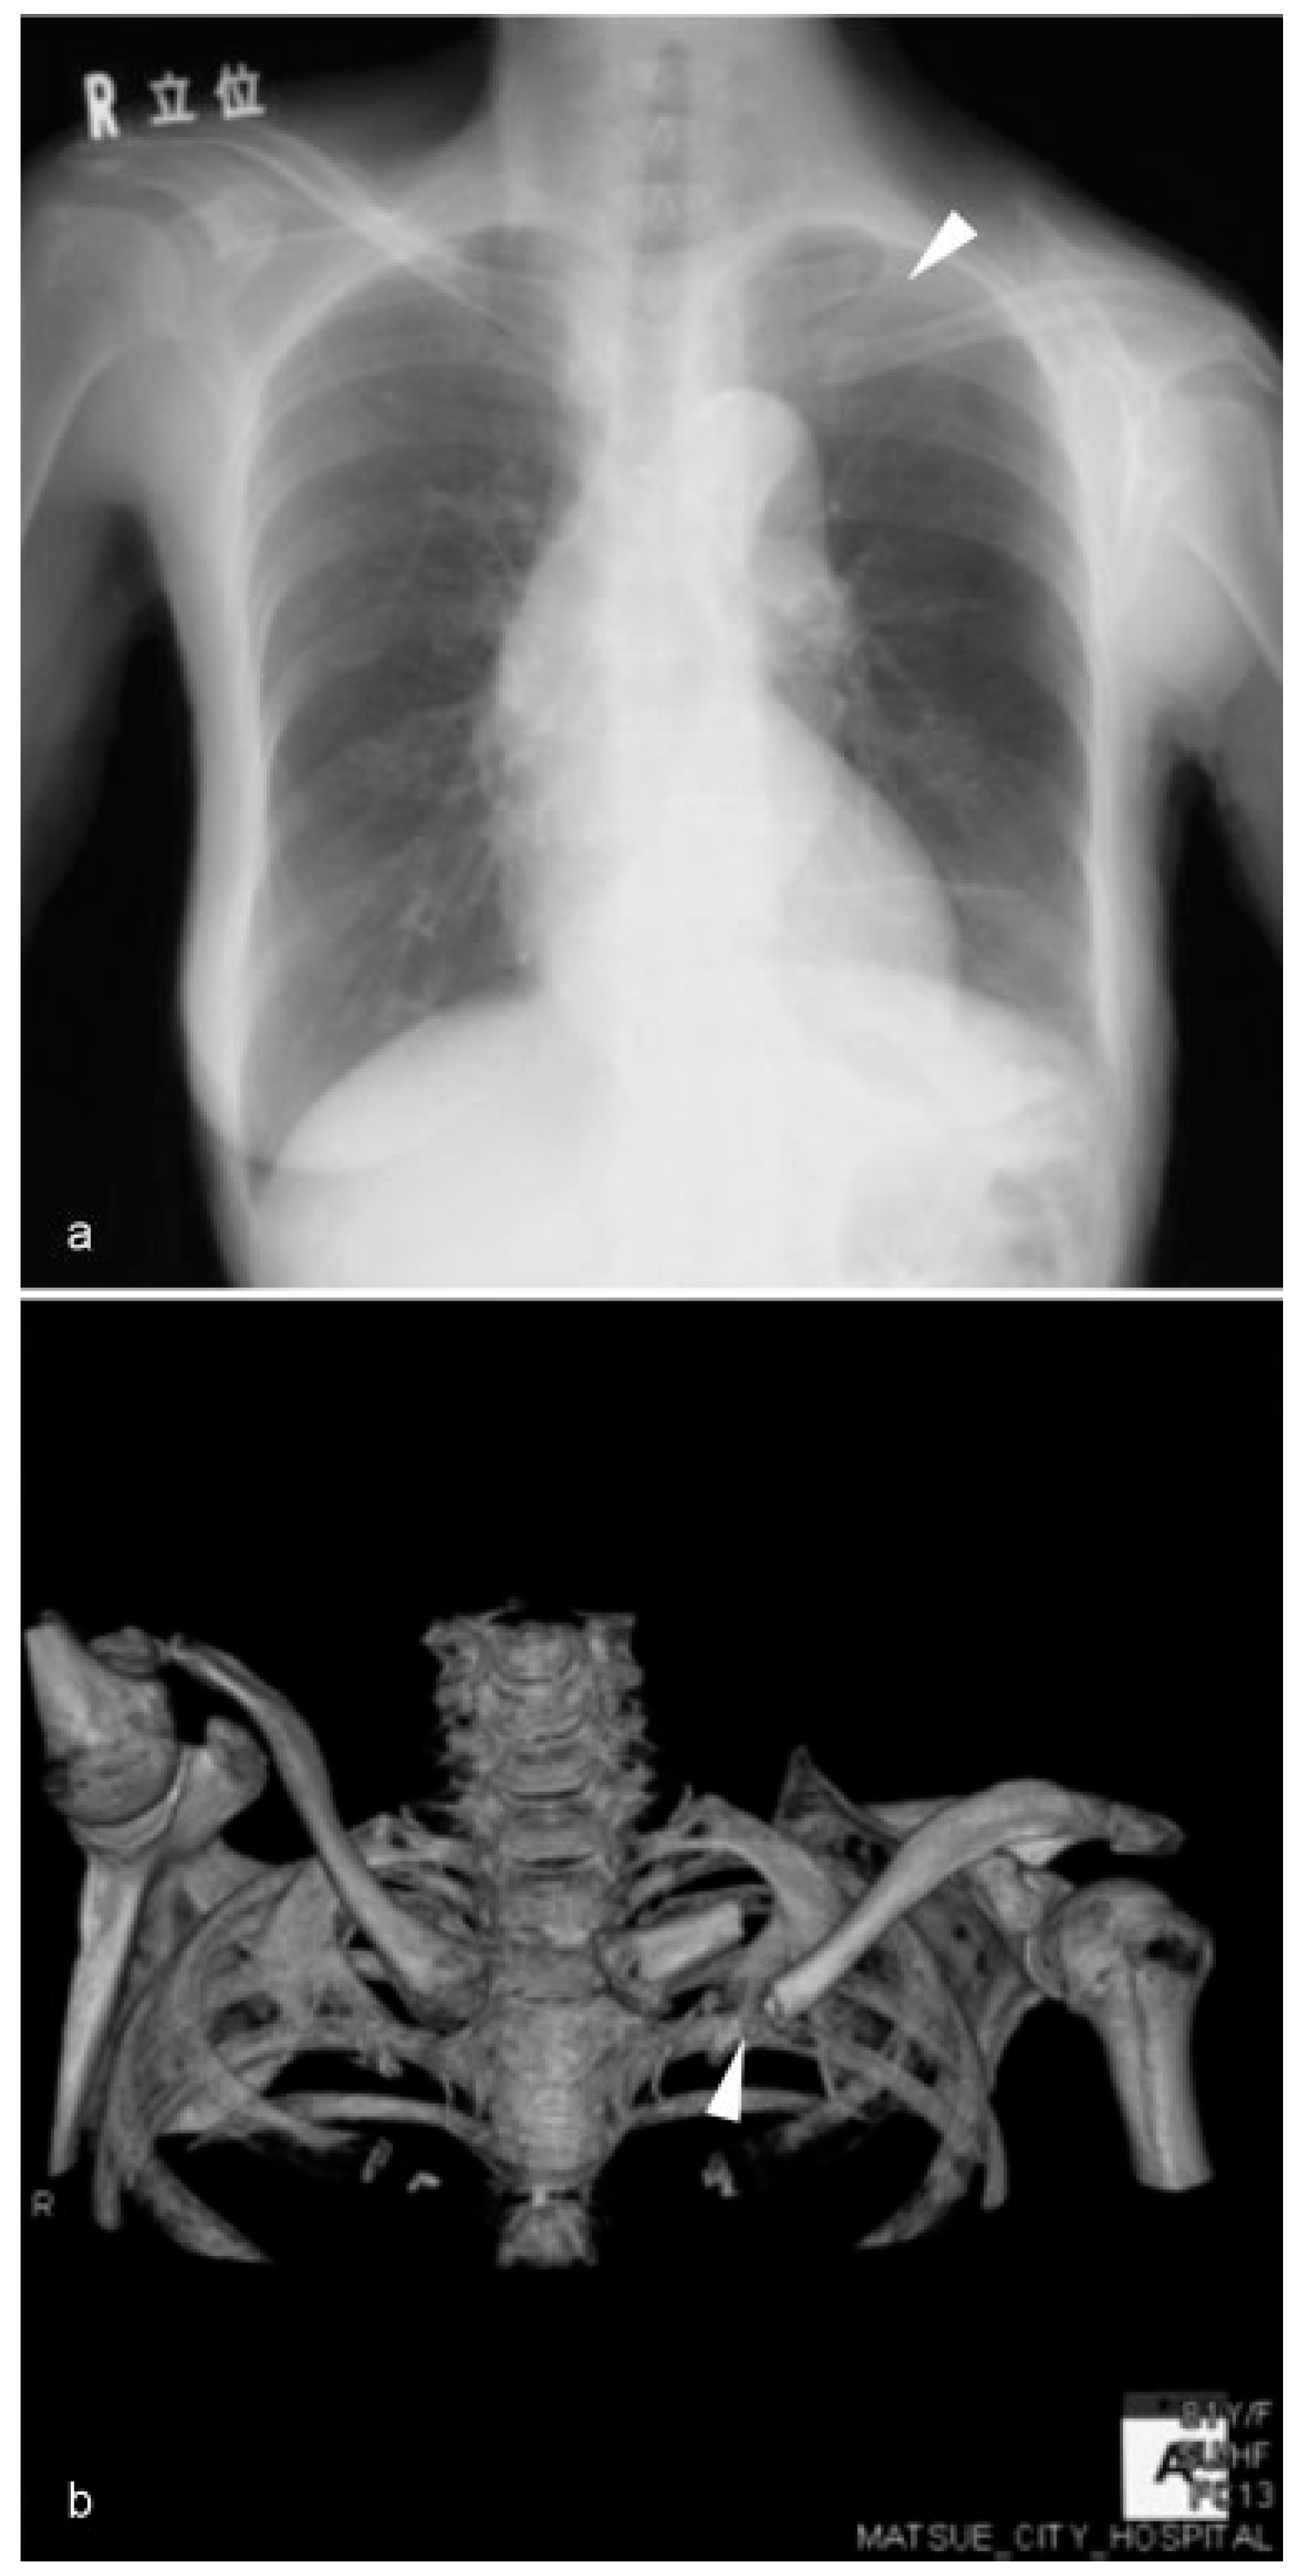

The surgical specimen showed lymphatic, vascular, and perineural invasions in the primary lesion and multiple cervical lymph node metastases. Consequently, postoperative radiotherapy to the primary site and whole neck was scheduled. Concurrent chemotherapy was not administered because of her renal dysfunction. The primary and cervical site was irradiated at a dose of 50.4 Gy. The supraclavicular site and whole clavicle were not irradiated (Figure 3).

Figure 3. Radiation field of the primary and cervical sites. The whole clavicle was outside the radiation field.

Cmtr 11 00024 g003